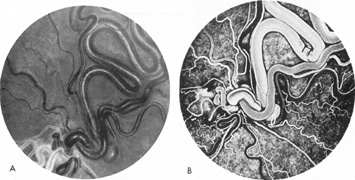

SUPRATENTORIAL

From 85% to 90% of AVMs are in the supratentorial compartment and are supplied primarily by the carotid circulation (Figs. 7 and 8). The remainder are supplied by the vertebrobasilar system. The approximate frequency of location is as follows: frontal, 22%; temporal, 18%; parietal, 27%; occipital, 5%; and deep intraventricular or paraventricular, 18%. The intracerebral site of the malformation does not necessarily indicate that there will be signs referable to that area simply from the mass effect of the malformation. Clinical features primarily result from subarachnoid hemorrhage or intraparenchymal hemorrhage with hematoma formation.

Fig. 7. Supratentorial arteriovenous malformation in a 28-year-old woman with a history of focal motor seizures for many years and a recent subarachnoid hemorrhage. A: Lateral projection carotid arteriogram demonstrating a huge deep hemispheral arteriovenous malformation. B: Frontal projection. C: Fundus photograph showing anomalous tortuous vasculature in each eye. No retinal arteriovenous shunt was detectable.

Fig. 8. Multiple supratentorial arteriovenous malformations (AVMs). A: Lateral projection of left carotid arteriogram shows dilated afferent artery (solid arrow) feeding the right hemispheric parietal AVM (open arrow). B: Right carotid injection fills a second, more posteriorly located, parietooccipital AVM (open arrow), which drains immediately to markedly dilated cortical veins (curved arrow).

In general, when hemorrhage occurs involving a portion of the visual radiations, a homonymous visual field defect is to be expected. Selective involvement of the anterior visual pathways may occur either with extensive venous angiomas at the base of the brain or as part of the Wyburn-Mason syndrome (see later), with direct involvement of the optic nerve, chiasm, or tract. Other variants such as congenital cavernous hemangiomas may involve the anterior visual pathways,68 as may intraparenchymal cryptic AVMs69 and present as symptomatic visual loss also resulting from hemorrhage and hematoma. Amaurosis fugax may even be the presenting symptom of supratentorial AVMs when blood is shunted to the meningeal circulation from the ophthalmic artery.70 When supratentorial AVMs drain into dural venous sinuses or the vein of Galen, distant ocular effects evolve, such as proptosis71 or ophthalmoplegia72 because of arterialization of cavernous sinus complex.

Of particular interest are those AVMs that involve the occipital lobe (Fig. 9). The clinical differentiation of migraine from a cerebral AVM was previously regarded as difficult because the clinical features of occipital lobe AVMs include visual phenomena or headaches. However, in most cases the clinical distinction is possible. In 26 cases with occipital AVM, two distinct syndromes were defined in 18 patients: occipital epilepsy and occipital apoplexy.73 Focal seizures with occipital malformations consist of elementary visual sensations similar to the phenomena evoked by direct cortical stimulations. When seizure activity occurs in the striate cortex (area 17), the patient usually reports sensations of moving lights in the right or left homonymous fields. The sensations are poorly formed, episodic, usually brief, sometimes colored, and unassociated with the angular, scintillating figures so characteristic of migrainous cortical phenomena. Epileptic discharges from areas 18 and 19 cause photopsias that are unlikely to remain stationary and to flicker rapidly. The epileptic photopsias usually last only seconds; occasionally they last for a few minutes before the onset of a generalized seizure. In other instances only the brief visual episodes occur without spreading to produce a generalized seizure. Momentary dimming or blindness in one or both homonymous fields may be experienced with seizure activity in the occipital areas.

Fig. 9. Carotid arteriogram of an occipital lobe arteriovenous malformation (AVM). Lateral (A) and frontal (B) projections demonstrating a small occipital AVM (arrow). The patient was a 23-year-old woman who presented with severe apoplectic unilateral headache, total left homonymous hemianopia, and mild nuchal rigidity. Despite xanthochromic cerebrospinal fluid, she was initially diagnosed elsewhere as having migraine. An AVM was successfully resected, and a small occipital lobe hematoma was removed.